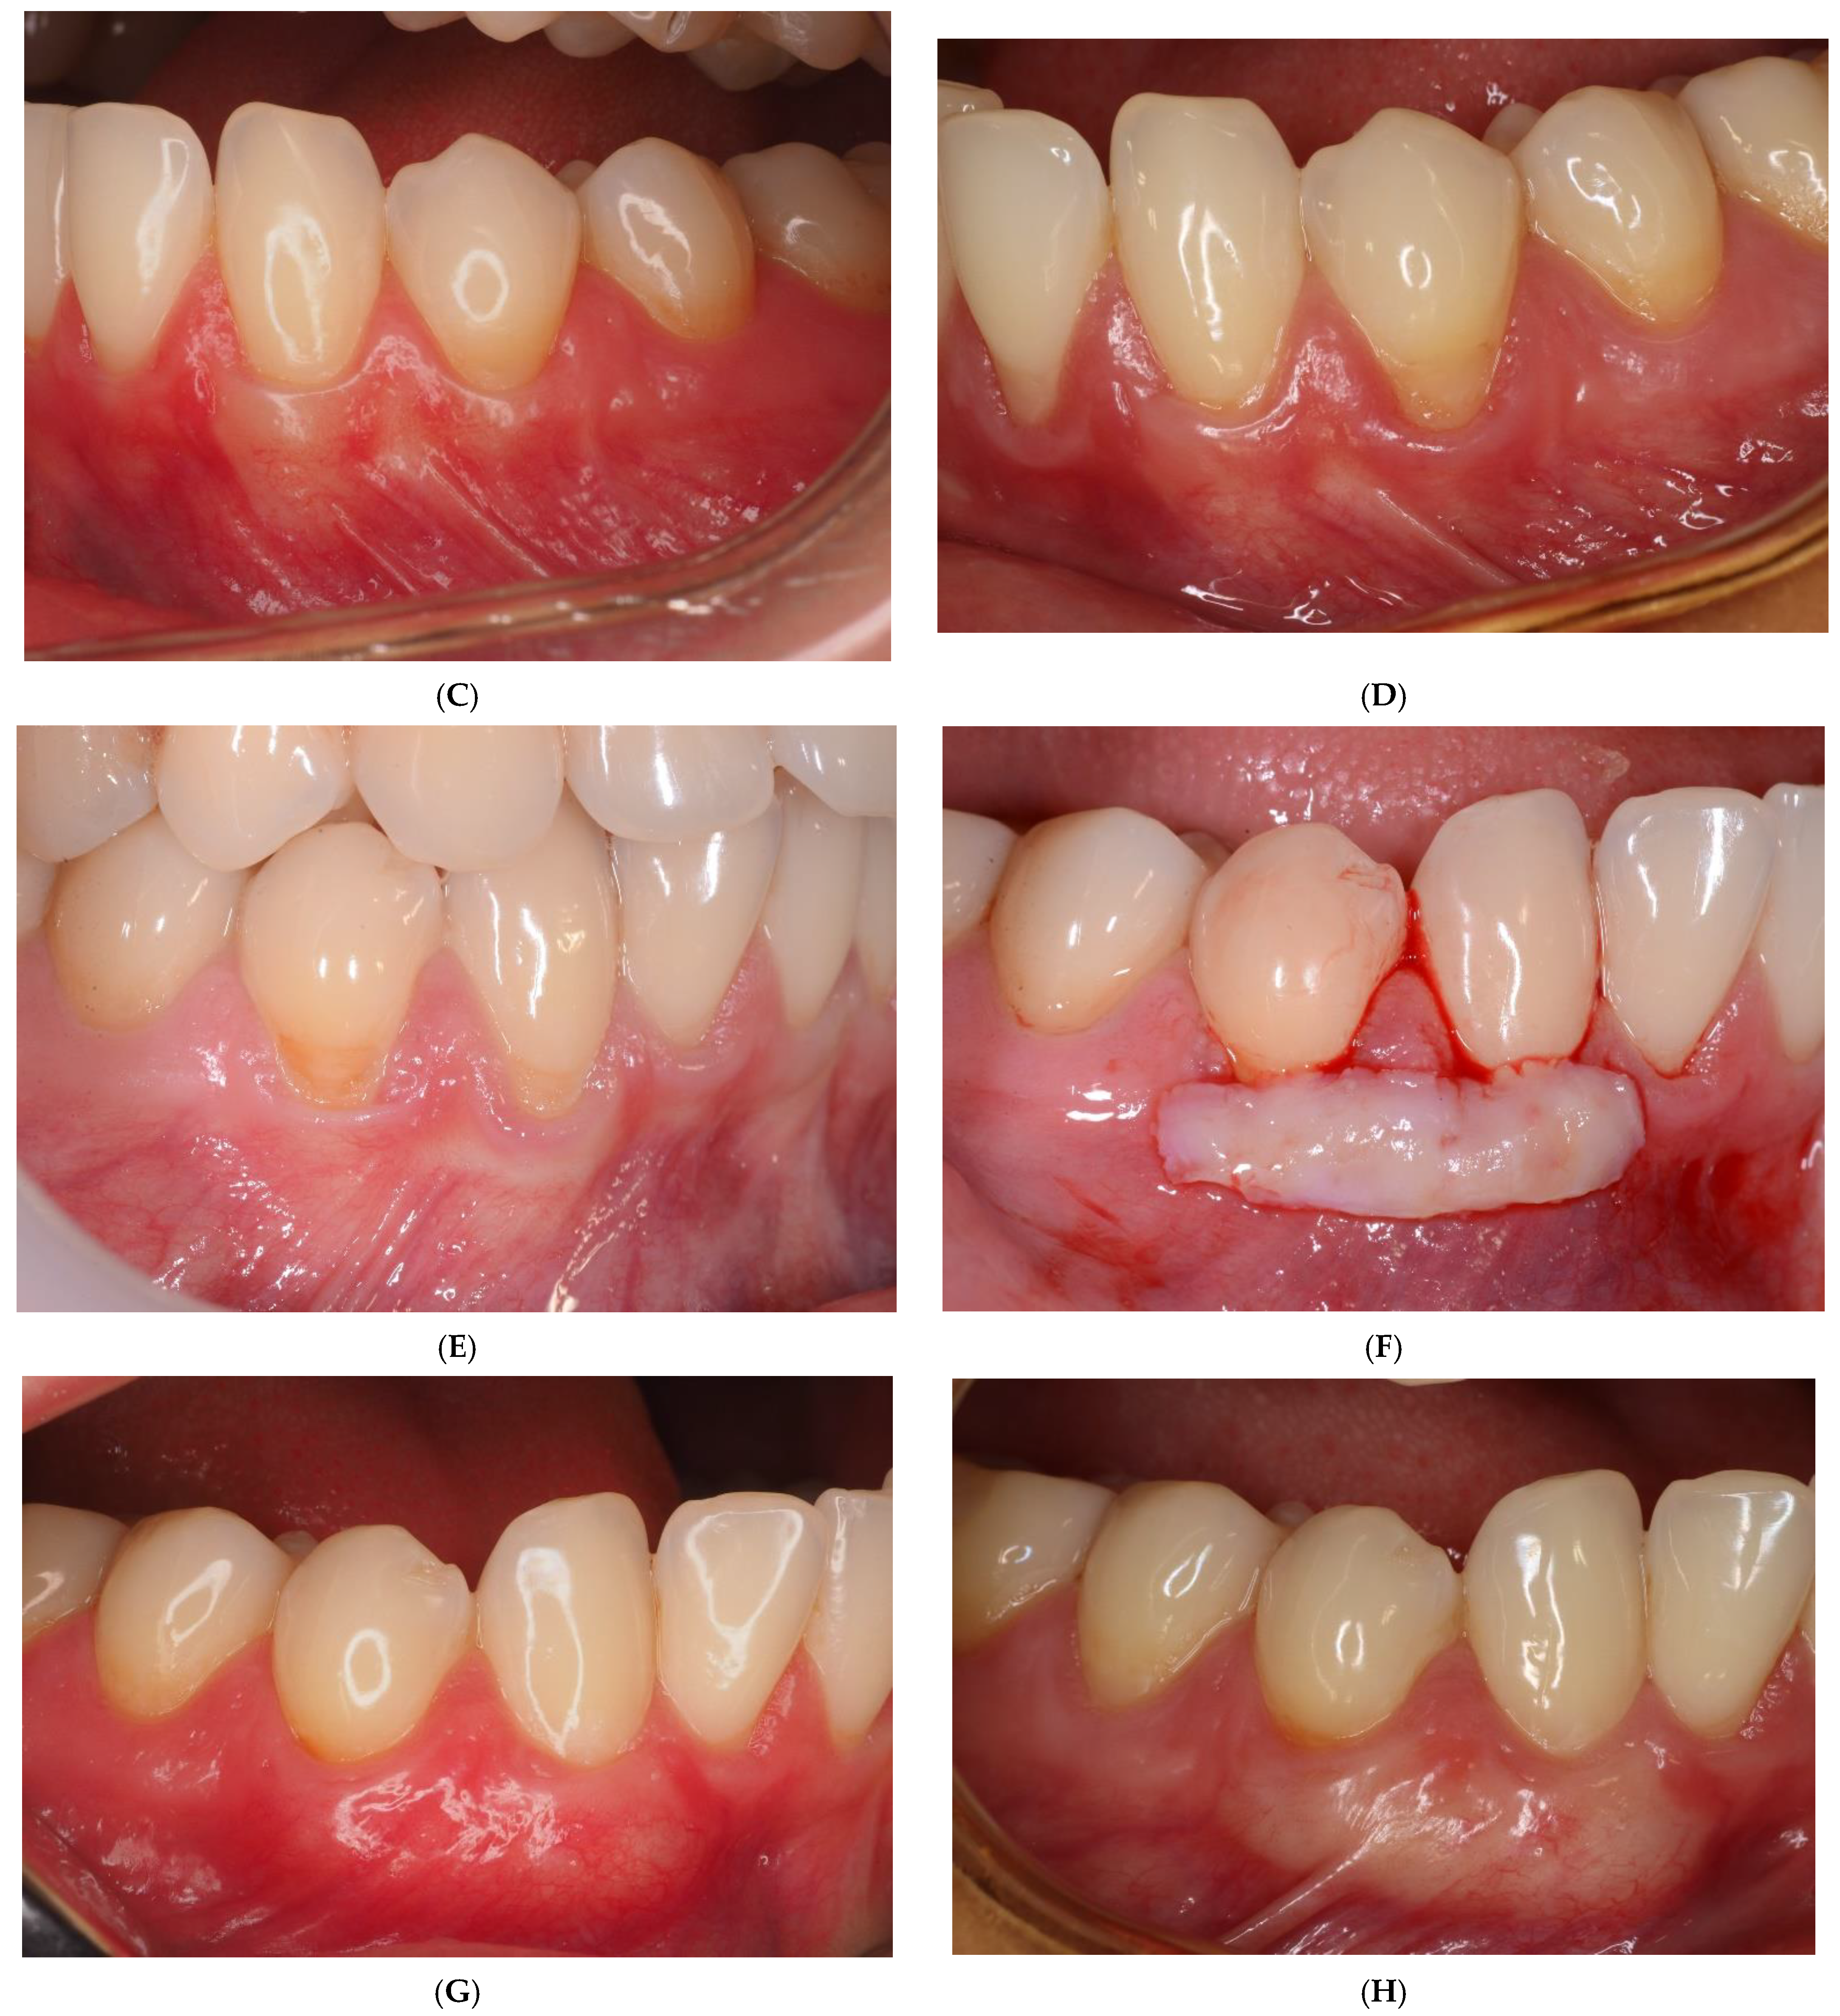

Figure 2. (A) Baseline CM side: the canine and the first premolar with recessions on the left side in the lower jaw; (B) CM position; (C) postoperative (12 months) view; (D) postoperative (5 years) view; (E) baseline SCTG side: the canine and the first premolar with recessions on the right side in the lower jaw; (F) SCTG position; (G) postoperative (12 months) view; (H) postoperative (5 years) view.

The SCTG and CM were covered with a coronally advanced flap and secured with sling sutures using 6-0 non-resorbable monofilament suture (Ethilon®, Ethicon, Bridgewater, NJ, USA). The sutures were removed 2 weeks post-op (Figure 1 and Figure 2).